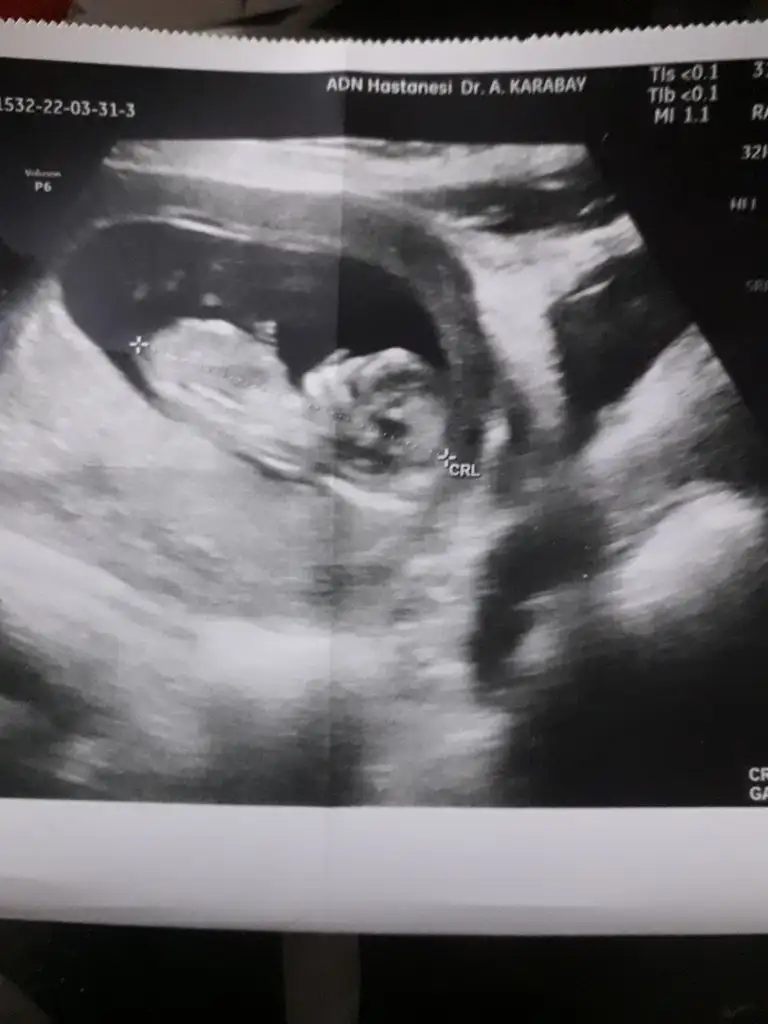

Kuzu prenses gibi duruyor sen ne hissediyorsun12 haftalık karından görüntü tahmin edebilir misiniz![]()

ben bile anlamadığım halde yüzünde kız güzelliği gördüm :)Merhabalar :) Biz 29. Haftaya girdik ama hala emin olamadı doktorum. En son 13 haftalik fotoğrafı var bende ve karından çekildi. Sizin de fikrinizi merak ettim bir bakar mısınız![]()

Prenses gibi cnmMerhaba benimde karından bakıldı 11 haftalık resim pek net değil ama tahminde bulunurmusunuz